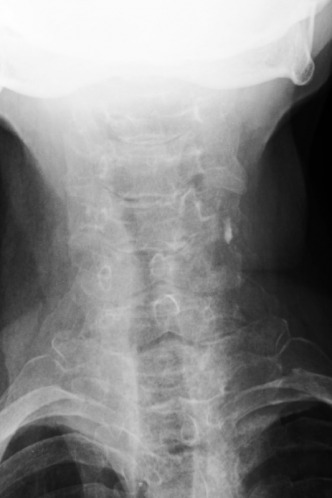

1. What is the key finding?

2. What is the etiology of the main finding - trauma, congenital, other?